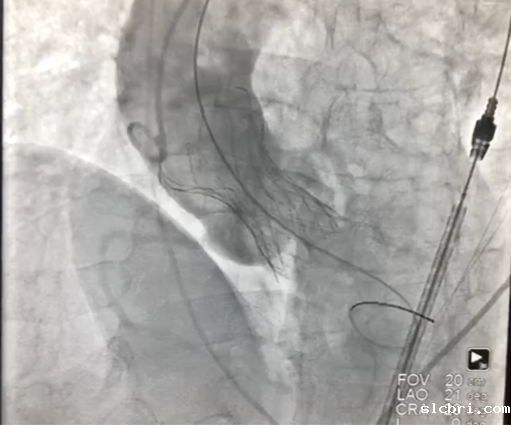

2、经左股动脉入路,顺利跨瓣后,选取20 mm球囊于180 bpm下快速起搏预扩,显示无漏,左、右冠脉未受影响,但可见左冠窦、无冠窦巨大钙化团块。

3、按照既定策略,选择24 mm VitaFlow微创瓣膜,于180 bpm快速起搏下,快速一次性释放。

4、术后心电监护未见传导阻滞,心超提示人工主动脉瓣工作良好,瓣叶启闭正常,主动脉瓣峰值流速2 m/s,平均跨瓣压差6 mmHg,轻度瓣周漏。

主动脉根部造影示瓣膜位置合适(深度2 mm),轻度瓣周漏。遂释放瓣膜,撤回脑保护装置,手术圆满成功。